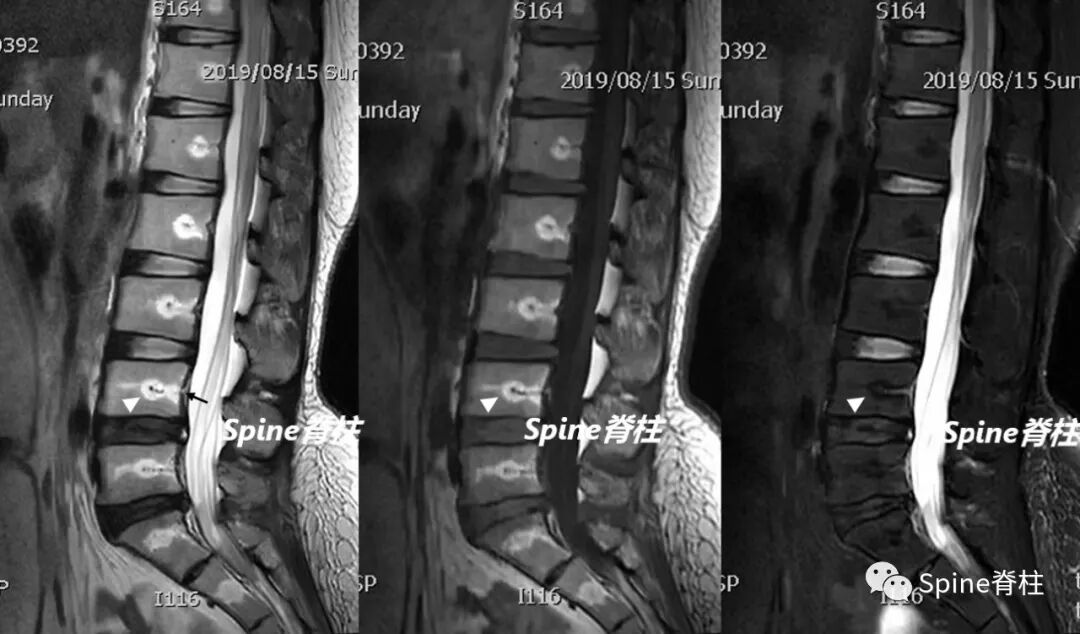

此外,还有其他容易识别的伪影。骨科金属植入物在高场强时会引起更广泛伪影,表现为低信号强度和脊髓变形。外周信号伪影因线圈单元与扫描范围不匹配产生,有多种表现形式。拼接伪影在脊柱扫描拼接中,因金属异物、参数不一致等因素,导致上下两段对比度不一致。同时,阅片时还需注意不要忽略正常解剖结构,如椎基静脉孔和神经血管脂肪簇等。

蓝色箭头所指的是由脊髓腔内脑脊液流动所形成的流动伪影,白色箭头所指的则是截断伪影。蓝色和白色箭头所呈现的征象均属于伪影,椎管和脊髓实际上是正常的,而星号区域为 L1 椎体血管瘤。